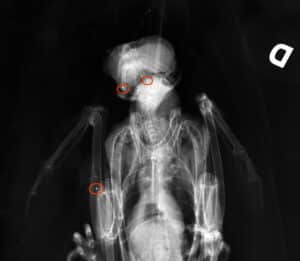

Le 8 août 2021, un Vautour fauve a été retrouvé mort dans le Parc National des Cévennes. Le corps de l’animal était criblé d’une vingtaine de plombs. Depuis 2013, la LPO (Ligue pour la Protection des Oiseaux) a recensé au moins 20 vautours victimes de tirs dont 9 rien que sur le territoire du parc. Et, les vautours ne sont pas les seuls rapaces victimes de tirs. Nombre d’Aigles royaux, Circaètes Jean Le Blanc, Faucons pèlerins, Buses variables et de Grand-Duc d’Europe sont pris pour cibles par des tirs de plombs.

D’après un communiqué de la LPO, « le 14 juillet, deux circaètes ont été conduits à la clinique vétérinaire de Ganges (Hérault) : l’un est arrivé mort victime d’un tir fatal ; l’autre, encore vivant, a été traversé par une salve de plombs (organes et plumes). Le 26 mai, dans le Parc national des Cévennes, un Faucon pèlerin a été découvert blessé à l’aile sur la commune d’Ispagnac (Lozère). Souffrant, il a finalement été euthanasié. »